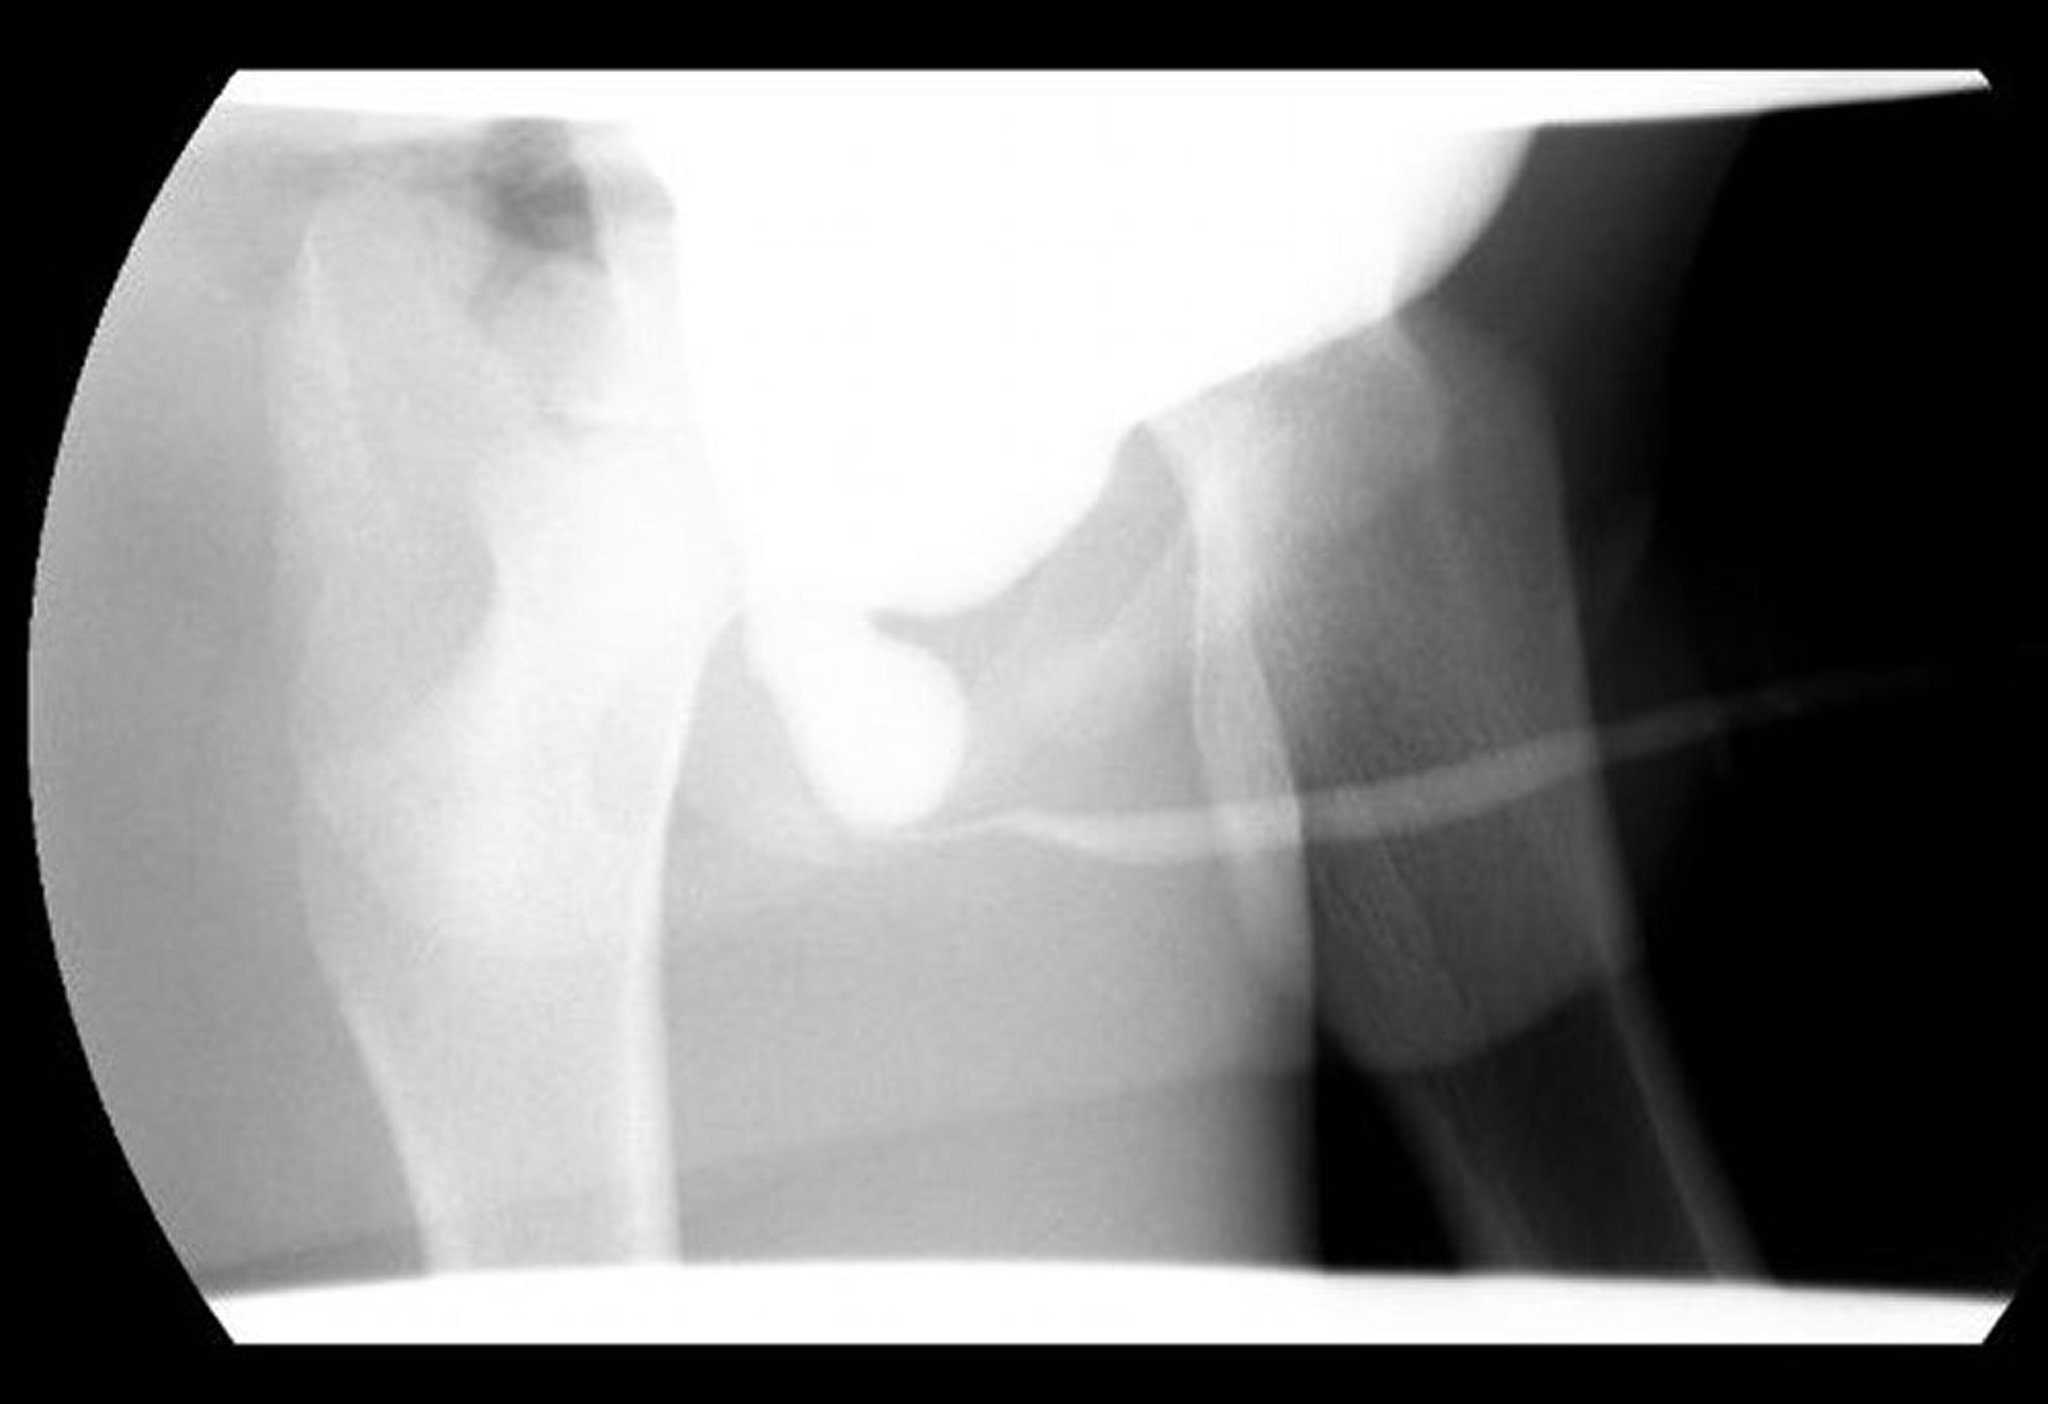

Valvules de l'urètre postérieur

Cette image de cysto-urétrographie mictionnelle montre une dilatation de l'urètre postérieur avec une obstruction distale due à des valvules urétrales postérieures.

Image courtoisie de Drs. Ronald Rabinowitz et Jimena Cubillos.